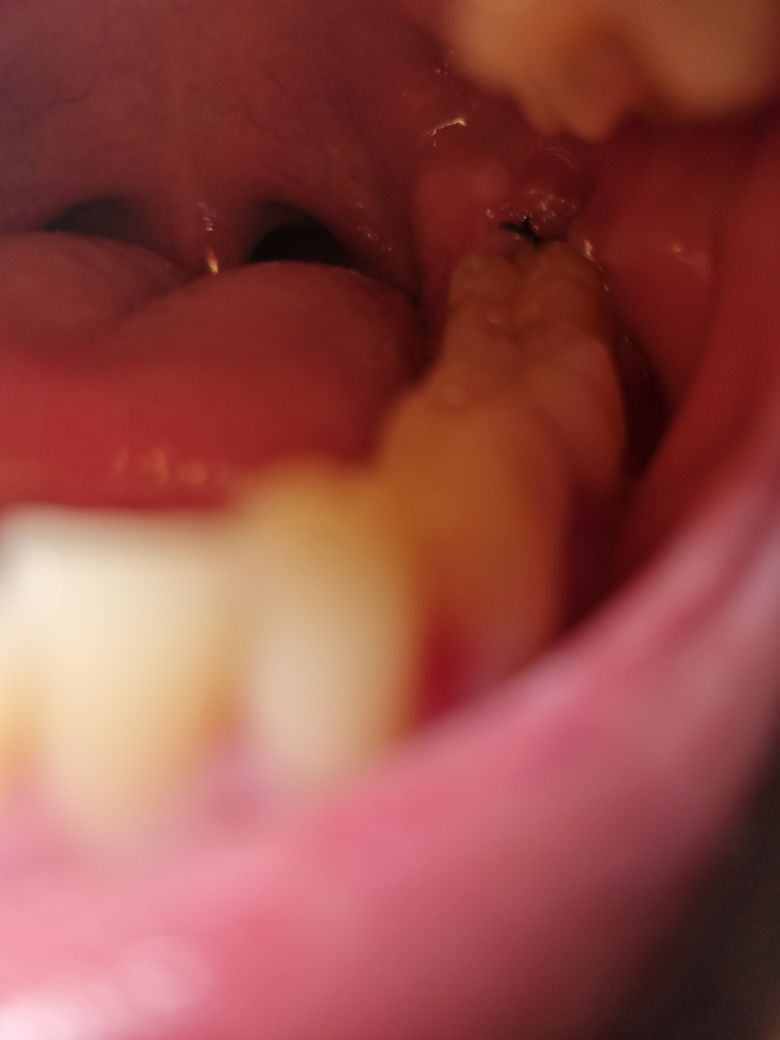

사랑니 발치 7일차 혈병 떨어졌는데 괜찮나요?

오늘 실밥 풀으러 가기전에 한번 봤는데 어제까지만

해도 혈병이 하얗게 변해서 있었는데 오늘 보니까

사라져 있었습니다 괜찮은가요?

• 1번 째 사진